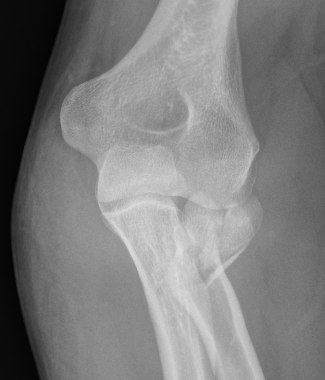

Completely displaced radial neck fracture

ORIF with plates